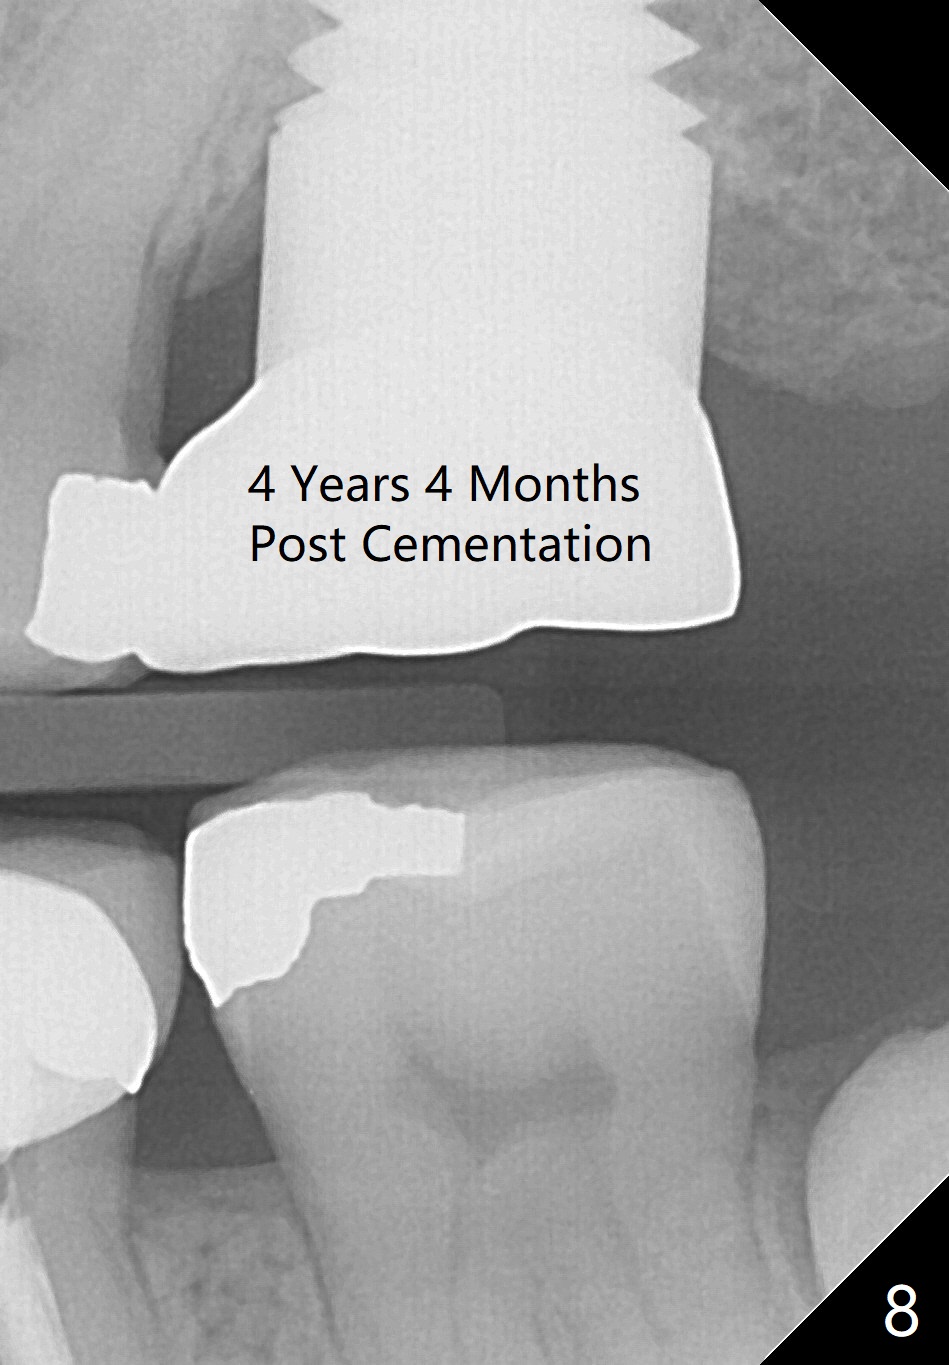

Four and a half months postop, bone resorption is slightly more severe (Fig.4) than immediately postop (Fig.3). Fig.5 is taken 1.5 weeks post cementation. Bone resorption appears to be halted 10 months (Fig.6) and 1.5 years (Fig.7) post cementation, respectively. The implant threads remain unexposed 4 years 4 months (Fig.8) and 5 years 4 months post cementation.